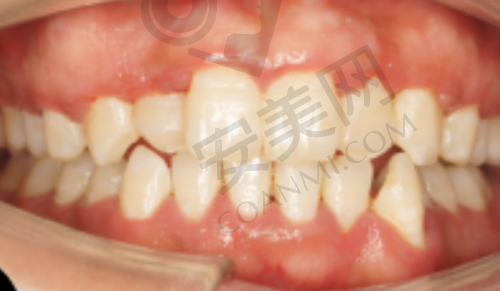

郑州白皮书口腔医院科室设置齐全,能够为患者提供一站式的口腔医疗服务。医院设有口腔种植中 心、口腔正畸中 心、口腔修复科、口腔内科、口腔外科等多个临床科室。从基础的洁牙、补牙、拔牙、洗牙、口腔检查,到复杂的种植牙、牙齿矫正、儿童龋齿治疗、根管治疗、牙周治疗等,医院都能提供全方面、个性化的治疗方案。例如,在口腔种植中 心,能够开展各种类型的种植手术,包括单颗种植、多颗种植、全口/半口牙颌种植等;口腔正畸中 心则提供隐形矫正、金属托槽矫正等多种正畸方式,满足不同患者的美观和治疗需求;儿童齿科专门为小朋友们打造,独立诊室结合动画投影、心理疏导,有效缓解儿童看牙恐惧,让孩子们能够轻松接受治疗。这样的科室设置,不仅让患者省心省力,更确保了治疗的连贯性和有效性。

种植牙是郑州白皮书口腔医院的核心优势项目。在技术团队方面,由郑创益医生领衔,他擅长All - on - 4/6半口种植、穿颧穿翼等高难度技术。医院采用瑞士ITI、瑞典Active、韩国DIO、美国3i、德国SKY等主流种植体,支持即刻负重技术,单颗种植手术时间可缩短至30分钟。在设备上,医院配备了精良的数字化设备,如3D口腔扫描仪、数字化种植系统、口腔CT等,误差控制在0.1毫米内,还引入了UNIC咬合重建系统,支持复杂病例的数字化方案设计。通过三维模型进行可视化设计,医生可以清晰地看到患者的口腔结构和牙齿缺失情况,从而制定出更加精细的种植方案。这种技术不仅能避开重要的解剖结构,如血管、神经等,降低手术风险,还能使植入位置、角度和深度更加精细,实现微创操作,大大缩短手术时间和修复周期。无论是简单的单颗牙缺失,还是复杂的全口牙列缺损,医院都能凭借精良的技术和专精的医生团队,为患者提供高质量的种植服务。